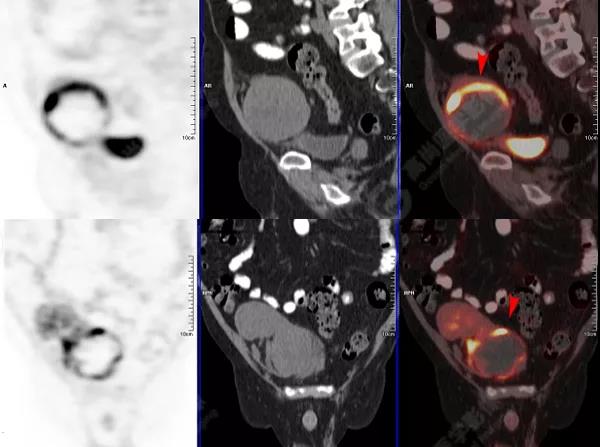

PET/CT檢查

↑移植腎下部等密度腫塊,代謝環(huán)狀增高,SUVmax13.4,中心代謝缺損